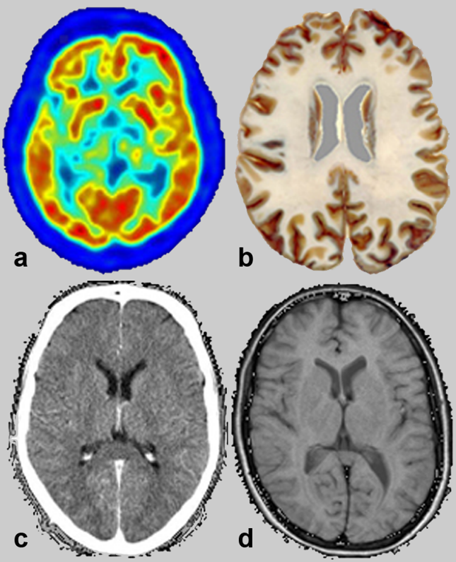

as imágenes adquiridas para fines médicos a menudo parecen si­mi­la­res; re­co­no­ce­mos fá­cil­mente que muestran la misma parte de la anatomía humana. Sin embargo, la información que estas imágenes contienen así como su re­so­lu­ción espa­cial son diferentes. Algunas imágenes muestran solo anatomía, otras mez­clan ana­to­mía e información metabólica, tal como lo prueban las cua­tro imá­ge­nes del cerebro en la Figura 02-01.

Figura 02-01:

Imágenes similares: cortes transversales a través del cerebro. Los métodos de adquisición va­rí­an:

(a) to­mo­gra­fía por emisión de positrones,

(b) una muestra anatómica,

(c) to­mo­gra­fía axial computarizada y

(d) imaginería por resonancia magnética. La principal discrepancia fun­da­men­tal entre las distintas téc­ni­cas se explica en la Tabla 02-01.